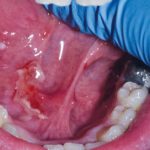

Home L’odontoiatria e le reazioni avverse a farmaci delle mucose orali Fig. 4C Caso clinico di lesioni lupus-like caratterizzate da aeree eritematose erosive su mucose geniene, alveolari e gengivali associate a papule e fini reticoli periferici asimmetrici.